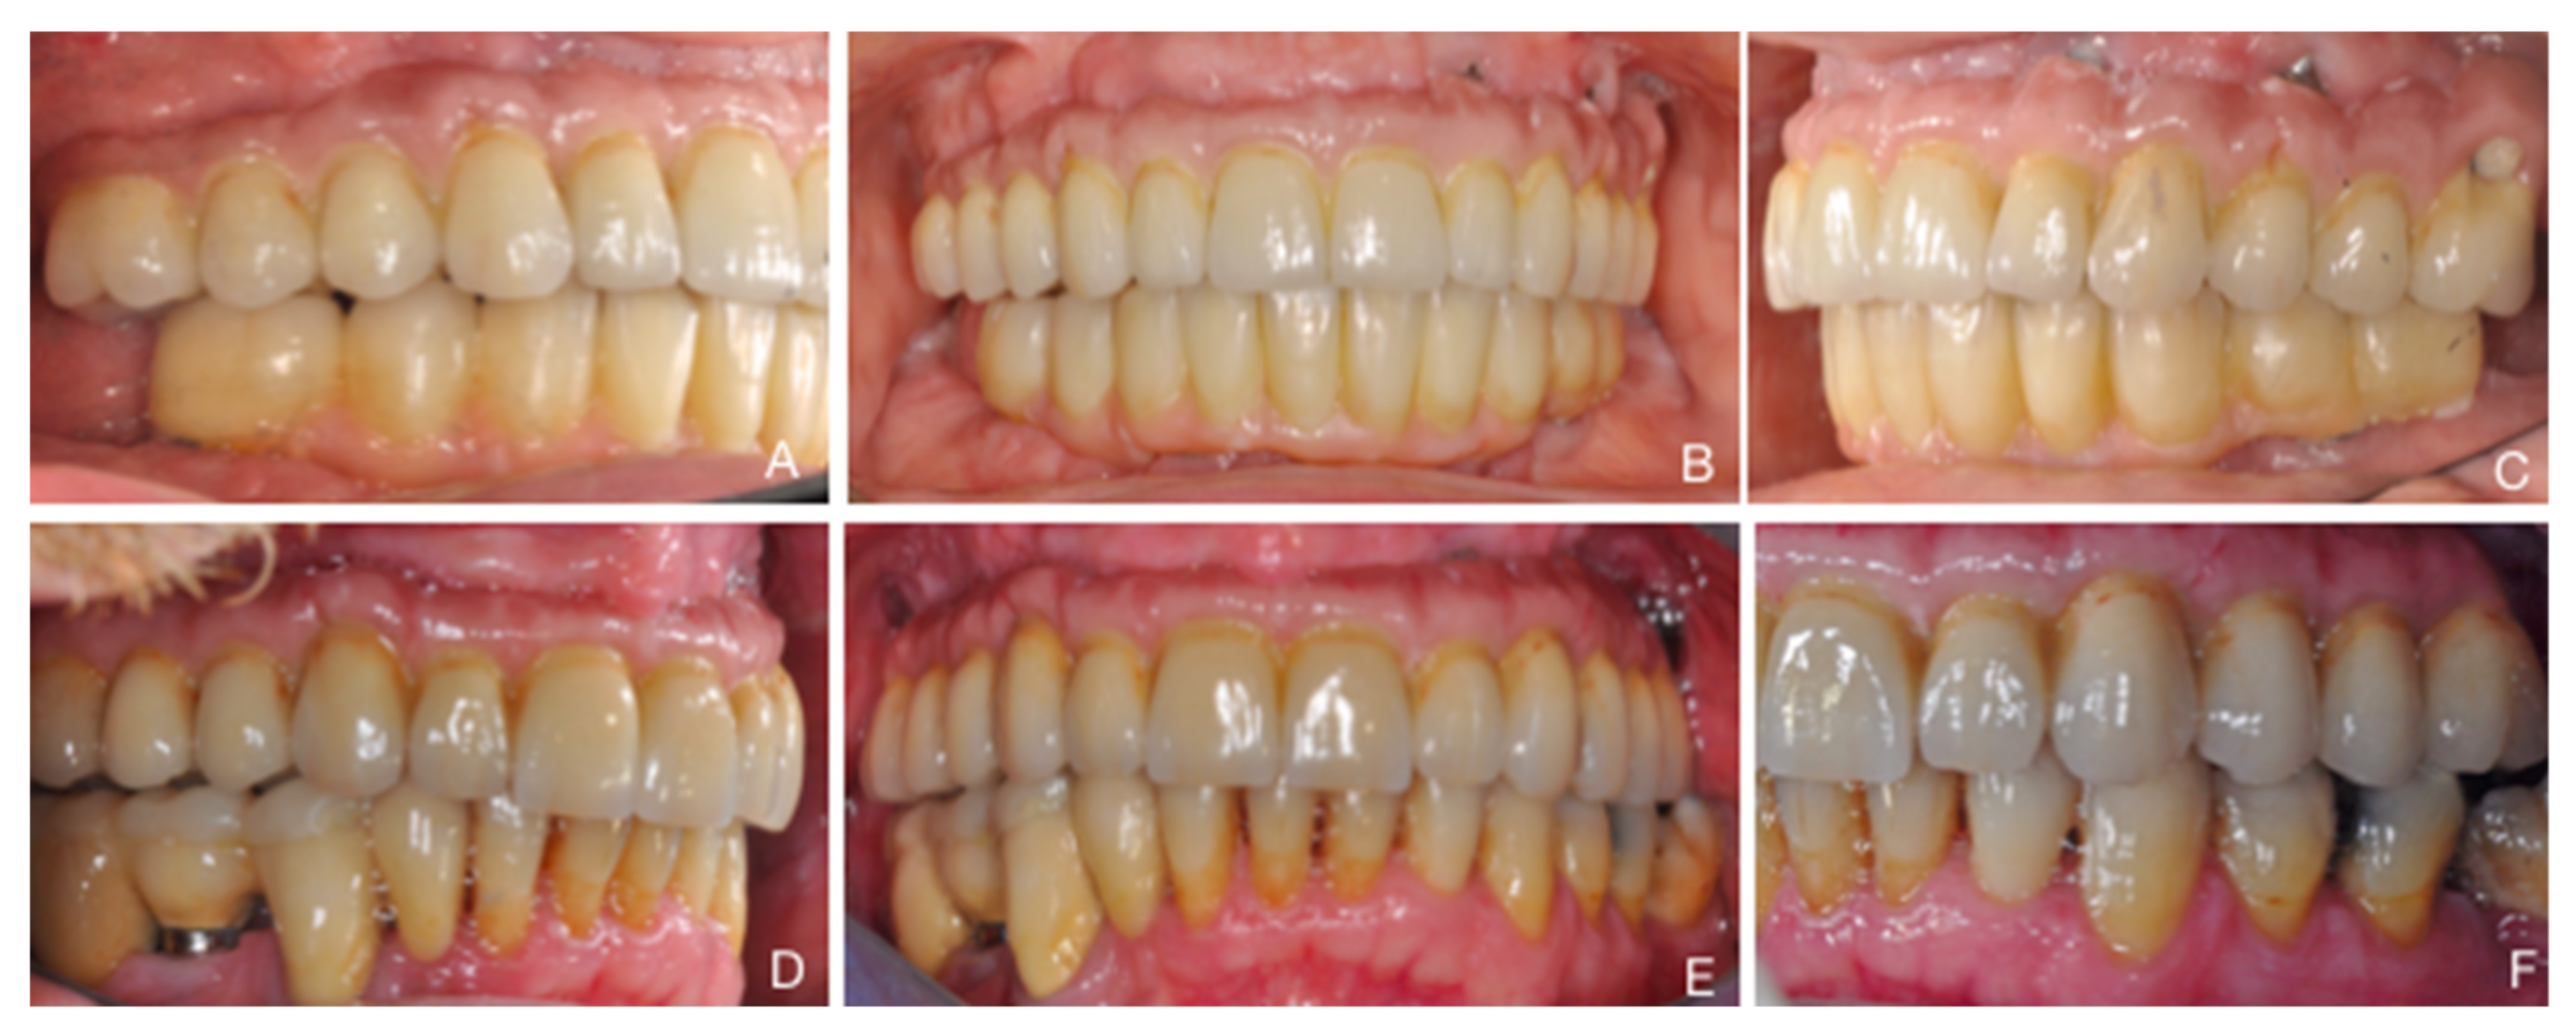

Two-Year Follow-Up of 4-mm-Long Implants Used as Distal Support of Full-Arch FDPs Compared to 10-mm Implants Installed after Sinus Floor Elevation. A Randomized Clinical Trial

2.9. Prosthetic Procedures

3. Results